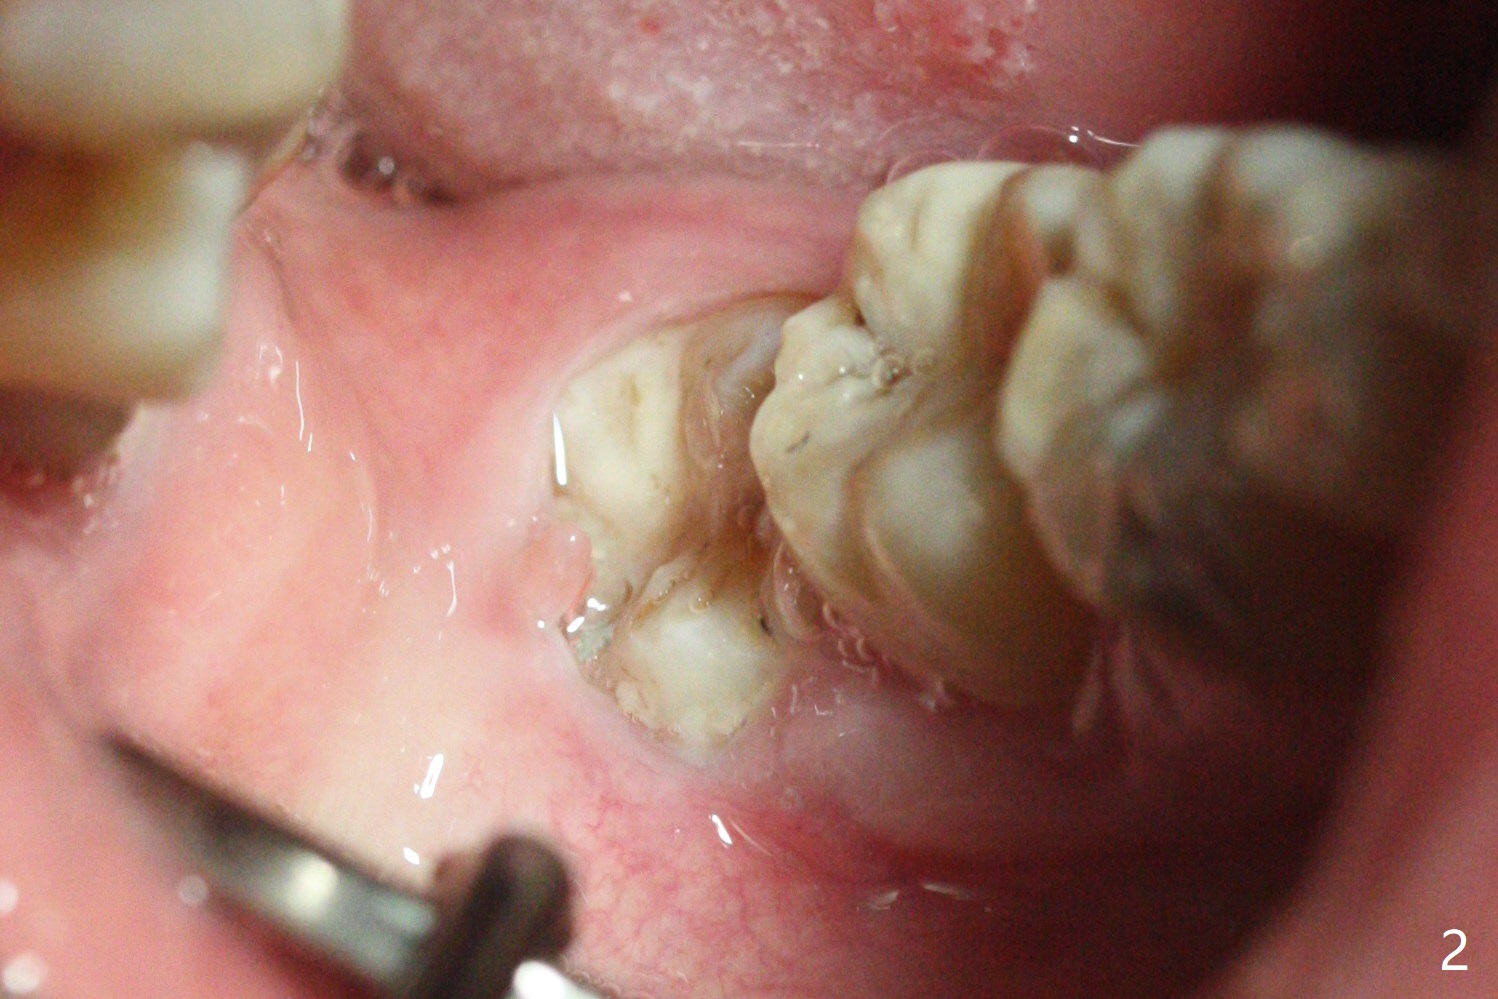

A 40-year-old man requests extraction of the teeth #17 and 32 (Fig.1). This case is designed to test that socket ossifies coronal when Collagen Plug is placed coronal. Release incision will be made both sides. Collagen plug will be placed at #32; none at #17. 4-0 PGA will be used to close the sockets. Photos will be taken immediate, 1 week, 1 month, and 3 months postop. PAs (sensor 1) will be taken immediate and 3 months postop. There is no wound dehiscence 1 week postop (Fig.6,7). The sockets reopen asymptomatic 3 weeks postop (Fig.8-11).